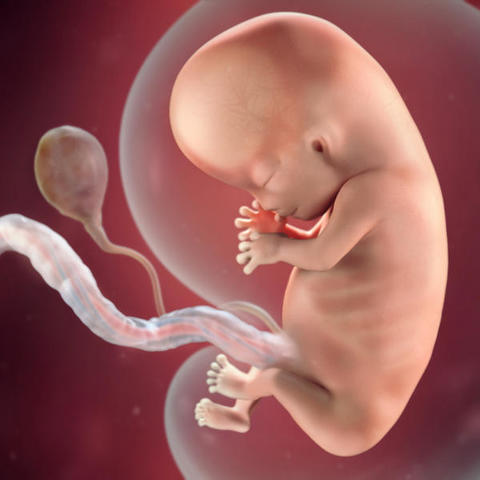

Fecundación

Surge cuando los espermatozoides(300 millones)penetran la tuba uterina y ahí sufren el proceso de capacitación , despúes se mueven por quimiotaxis hacia el ovocito secundario que se encuentra en las trompas de Falopio, donde pasa la fecundación, despues pasa la reacción acrosomica que le va a permitir la entrada a el ovocito, se produce la onda de calcio que hace que el ovocito siga su ciclo celular,la fecundación se concluye cuando hay una union del pronucleo femenino y masculino

• Period: to

1era SDG

El ovocito secundario se va a expulsar en el periodo de ovulación de la mujer , si no ocurre la fecundación este se degrada de 12-24 hrs por que no completa su segunda división mitotica, la cual tiene lugar cuando sucede la onda de calcio que hace que se forme un cuerpo polar también llamado pronucleo femenino, el cual cuando se une con el masculino sucede la fecundación , el cigoto va a secretar hCG el cual va a hacer que se mantenga el cuerpo luteo de la madre y no haya menstruación